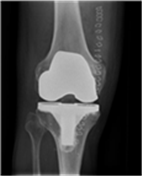

Til venstre ses en helprotese. Til højre ses helprotesen indsat i knæ.

Knæledsprotesen består af 3 dele

- Protesedelen på lårbenet er af rustfrit stål.

- Protesedelen på skinnebenet er af rustfrit stål eller titanium og består af en metalplade med køl, som går ned i marvhulen på skinnebenet. Oven på metalpladen sidder en del af hård plastik, som danner led med protesedelen på lårbenet.

- Protesedelen på knæskallen er af plastik.

Protesedelen kan enten gøres fast til knoglerne med knoglecement, der binder som lim eller uden knoglecement, hvor protesen har en overflade, som knoglen vokser ind i.

Den knoglecement, vi anvender, er af et fabrikat, som har været anvendt i mere end 30 år uden problemer.